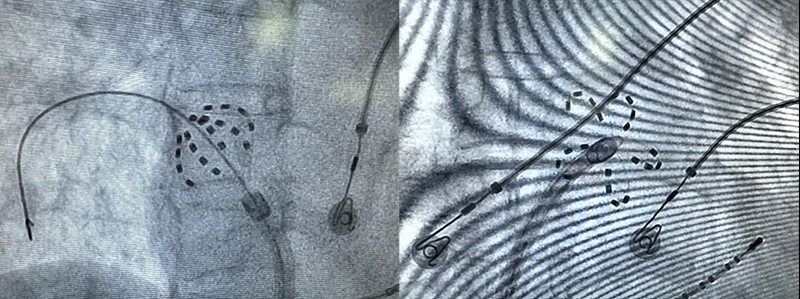

手术在麻醉科和介入手术室的全力配合下有序进行。陈广琴主任带领团队通过右股静脉成功穿刺房间隔,将FARAWAVE导管精确送入左心房。在短短38分钟内,团队便完成了双侧肺静脉、左房后壁及上腔静脉的电隔离。术中电位即刻验证,消融效果理想,手术取得了显著成功。

FARAWAVE导管以网篮和花瓣两种形态进行电隔离